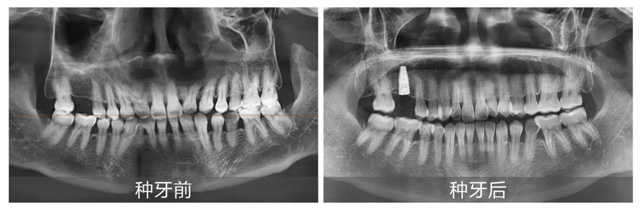

据胡女士所说,自己右上颌某颗牙齿因咀嚼硬物损坏而拔除,考虑到活动义齿要经常清洗,便决定选择更为长久且舒适的解决方案——种植牙,谈及自己的主刀医生——新桥口腔成都衣冠庙院区种植专科主任易华波,她表示:“易医生不仅专业,人也很随和,把自己的手术交给他做,我既安心又放心。”

上午10:37,手术正式开始。在衣冠庙院区大厅实时直播的大屏幕上,观众们可以清楚地看到易华波医生为胡女士实施局部麻醉、备洞、植入种植体和缝合等关键步骤,整个过程一气呵成。与此同时,衣冠庙院区咨询主管吴海燕也利用自己的专业知识,用简单易懂的语言为认真观摩的来宾们讲解了数字化种植手术步骤的要点、目的及新桥口腔舒适化种植牙金标准,助力顾客在手术全程放松舒适的状态下获得“好口福”。

上午10:45,手术圆满结束。令人惊叹的是,从打麻药到手术完成,用时不到10分钟,真正体现了新桥口腔数字化种植牙技术的高效与精准。

易华波医生对本次手术进行了简单总结:胡女士的手术相对简单,但即便如此,每一例种植牙手术前期方案的制定都至关重要。他表示,种植牙不仅仅是替换缺失牙齿,还要考虑口腔未来的整体健康和咀嚼功能的恢复,在手术过程中,我们需要确保种植体的位置、角度以及与周围牙齿的间隔,力求为每一位顾客带来最优质的诊疗体验。